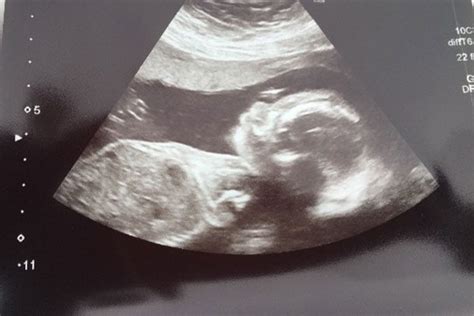

Hey guys, let’s talk about something super important and frankly, a bit nerve-wracking: the 20-week scan . This scan, often called the anomaly scan, is a big deal. It’s usually the most detailed ultrasound you’ll have during your pregnancy, and it’s designed to check on your little one’s development, looking at everything from their tiny fingers and toes to their major organs. It’s a time when many parents-to-be get really excited to see their baby and find out if they’re having a boy or a girl! But what happens when the scan reveals something unexpected, or, dare we say, bad news? This is a topic that pops up on forums like Reddit and Mumsnet quite a bit, and for good reason. Facing the possibility of complications or an unexpected diagnosis at this stage can be incredibly overwhelming. It’s natural to feel a whirlwind of emotions – shock, fear, sadness, anger, and confusion. You might find yourself replaying the scan in your head, wondering if anything could have been done differently, or if you missed any signs. The medical team performing the scan is highly trained to look for specific markers that might indicate a potential issue. They’ll be examining the baby’s brain, heart, lungs, kidneys, stomach, spine, and limbs, as well as the placenta and umbilical cord. If they spot something that doesn’t look quite right, they won’t just ignore it. They’ll usually have a discussion with you right there and then, or schedule a follow-up appointment with a specialist. It’s important to remember that sometimes what looks concerning on a scan might turn out to be nothing serious, or it might be something manageable. However, being prepared for the possibility of difficult news is part of the journey for some expectant parents. This article aims to shed some light on what to expect if you receive bad news at your 20-week scan, how to navigate the emotional rollercoaster, and where to find support. We’ll delve into the common reasons for concern, the next steps involved, and how to cope with the uncertainty and challenges that may arise. It’s a heavy topic, but having information can be a powerful tool in managing anxiety and making informed decisions.

Alright, let’s dive deeper into the 20-week anomaly scan , because understanding what the sonographer is actually looking for can help demystify the process and perhaps ease some of the pre-scan jitters. This scan is pretty comprehensive, guys. The primary goal is to check for major structural abnormalities in the baby’s development. Think of it as a detailed road map of your baby’s anatomy. They’ll meticulously examine the baby’s head, checking the brain for development and structure. They’ll look at the face, including the lips and palate, to check for cleft lip or palate. The heart is a big focus, with them assessing the four chambers and the major blood vessels to ensure they’re forming correctly. They’ll also examine the baby’s abdomen, looking at the stomach, intestines, and kidneys. The spine is checked for any gaps or abnormalities, and all four limbs – arms, legs, hands, and feet – are carefully counted and assessed. The placenta is checked for its position and to make sure it’s providing adequate blood flow to the baby, and the umbilical cord is examined for the correct number of blood vessels. It’s crucial to understand that this scan is a screening tool, not a diagnostic test for everything. While it’s incredibly thorough, it’s not foolproof. Some minor issues might not be visible on the scan, and some conditions only become apparent later in pregnancy or after birth. When the sonographer is performing the scan, they are looking for deviations from what is considered typical development. This could range from something relatively minor, like a slight difference in limb length that might resolve on its own, to more significant concerns like congenital heart defects, spina bifida, or certain genetic syndromes. They’re comparing the baby’s measurements and appearance against established growth charts and developmental milestones. If they notice something that falls outside the normal range, they are trained to flag it. This doesn’t automatically mean there’s a serious problem, but it does mean further investigation is often needed. For example, a bright spot in the baby’s heart might be a common finding that doesn’t affect the baby’s health, but it will be noted. Similarly, a slight delay in organ development might prompt a follow-up scan or referral to a specialist. The key takeaway here is that the medical professionals are doing their best to provide the healthiest possible outcome for you and your baby. They are trained observers, looking for subtle and not-so-subtle signs of potential issues. The goal isn’t to scare anyone, but to be proactive and catch anything that might require medical attention or planning before birth. It’s a vital part of prenatal care that provides invaluable information, even when that information is challenging to receive.